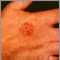

The main symptom of squamous cell skin cancer is a growing bump that may have a rough, scaly surface and flat reddish patches.

The bump is usually located on the face, ears, neck, hands, or arms, but may occur on other areas.

A sore that does not heal can be a sign of squamous cell cancer. Any change in an existing wart, mole, or other skin lesion could be a sign of skin cancer.

A lesion on the skin may indicate a squamous cell carcinoma. A biopsy and examination of the lesion can confirm whether it is squamous cell cancer.